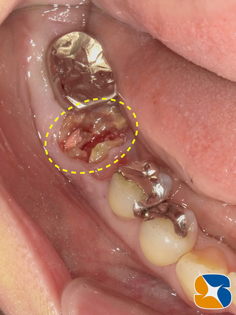

後日ブリッジを外してみると、ブリッジの土台の歯根が見事に粉々に砕けていました。

砕けた歯根を抜歯した後、続けてインプラントを同日に移植しました。